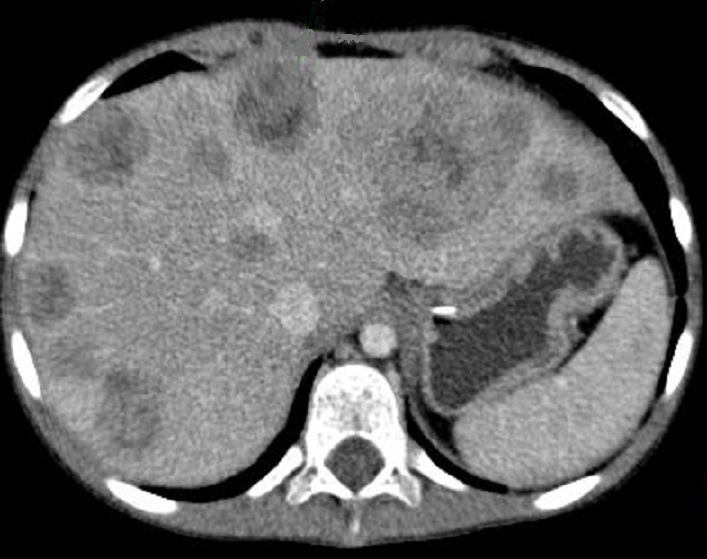

Le pancreatoblastome est la tumeur pancreatique

metastase hepatique d'une pancreatoblastome avec

aspect des metastases hypodenses heterogenes

disseminer au foie droit et gauche |

|